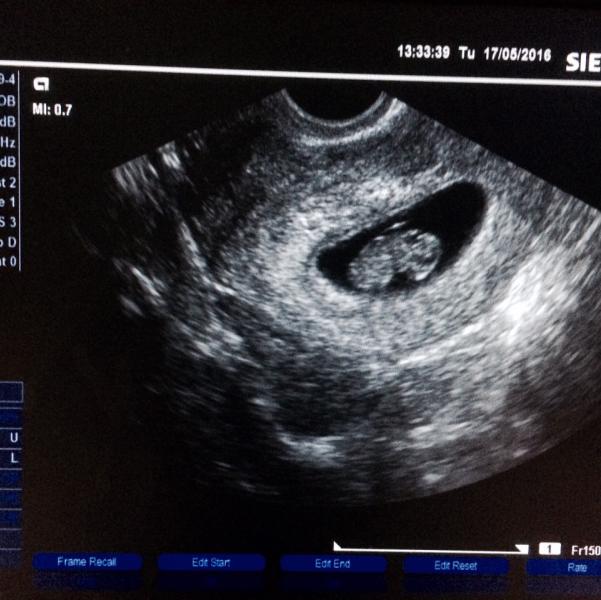

Всем привет красотки 👸🏼 Сегодня нам 8,6 неделек 🍼 Очень переживала по поводу бежевых выделений , и зря 😍👍🏻Сходила на приём к врачу 🏩🏥 Результаты анализов хорошие , кроме мазка ( вагинальный кандидоз : молочница + эрозия ) 📓 Отправила доктор на УЗИ , дабы исключить угрозу : ктр 21 мм , желточный мешок 6 мм , зев закрыт, тонуса и гематом нет , а самое главное сердечко бьется, вертимся и крутимся , ели поймали чтобы запечатлить и то получилось спинкой 😁💓💓💓 По результату УЗИ нам поставили 9 неделек 🍼👶🏼...